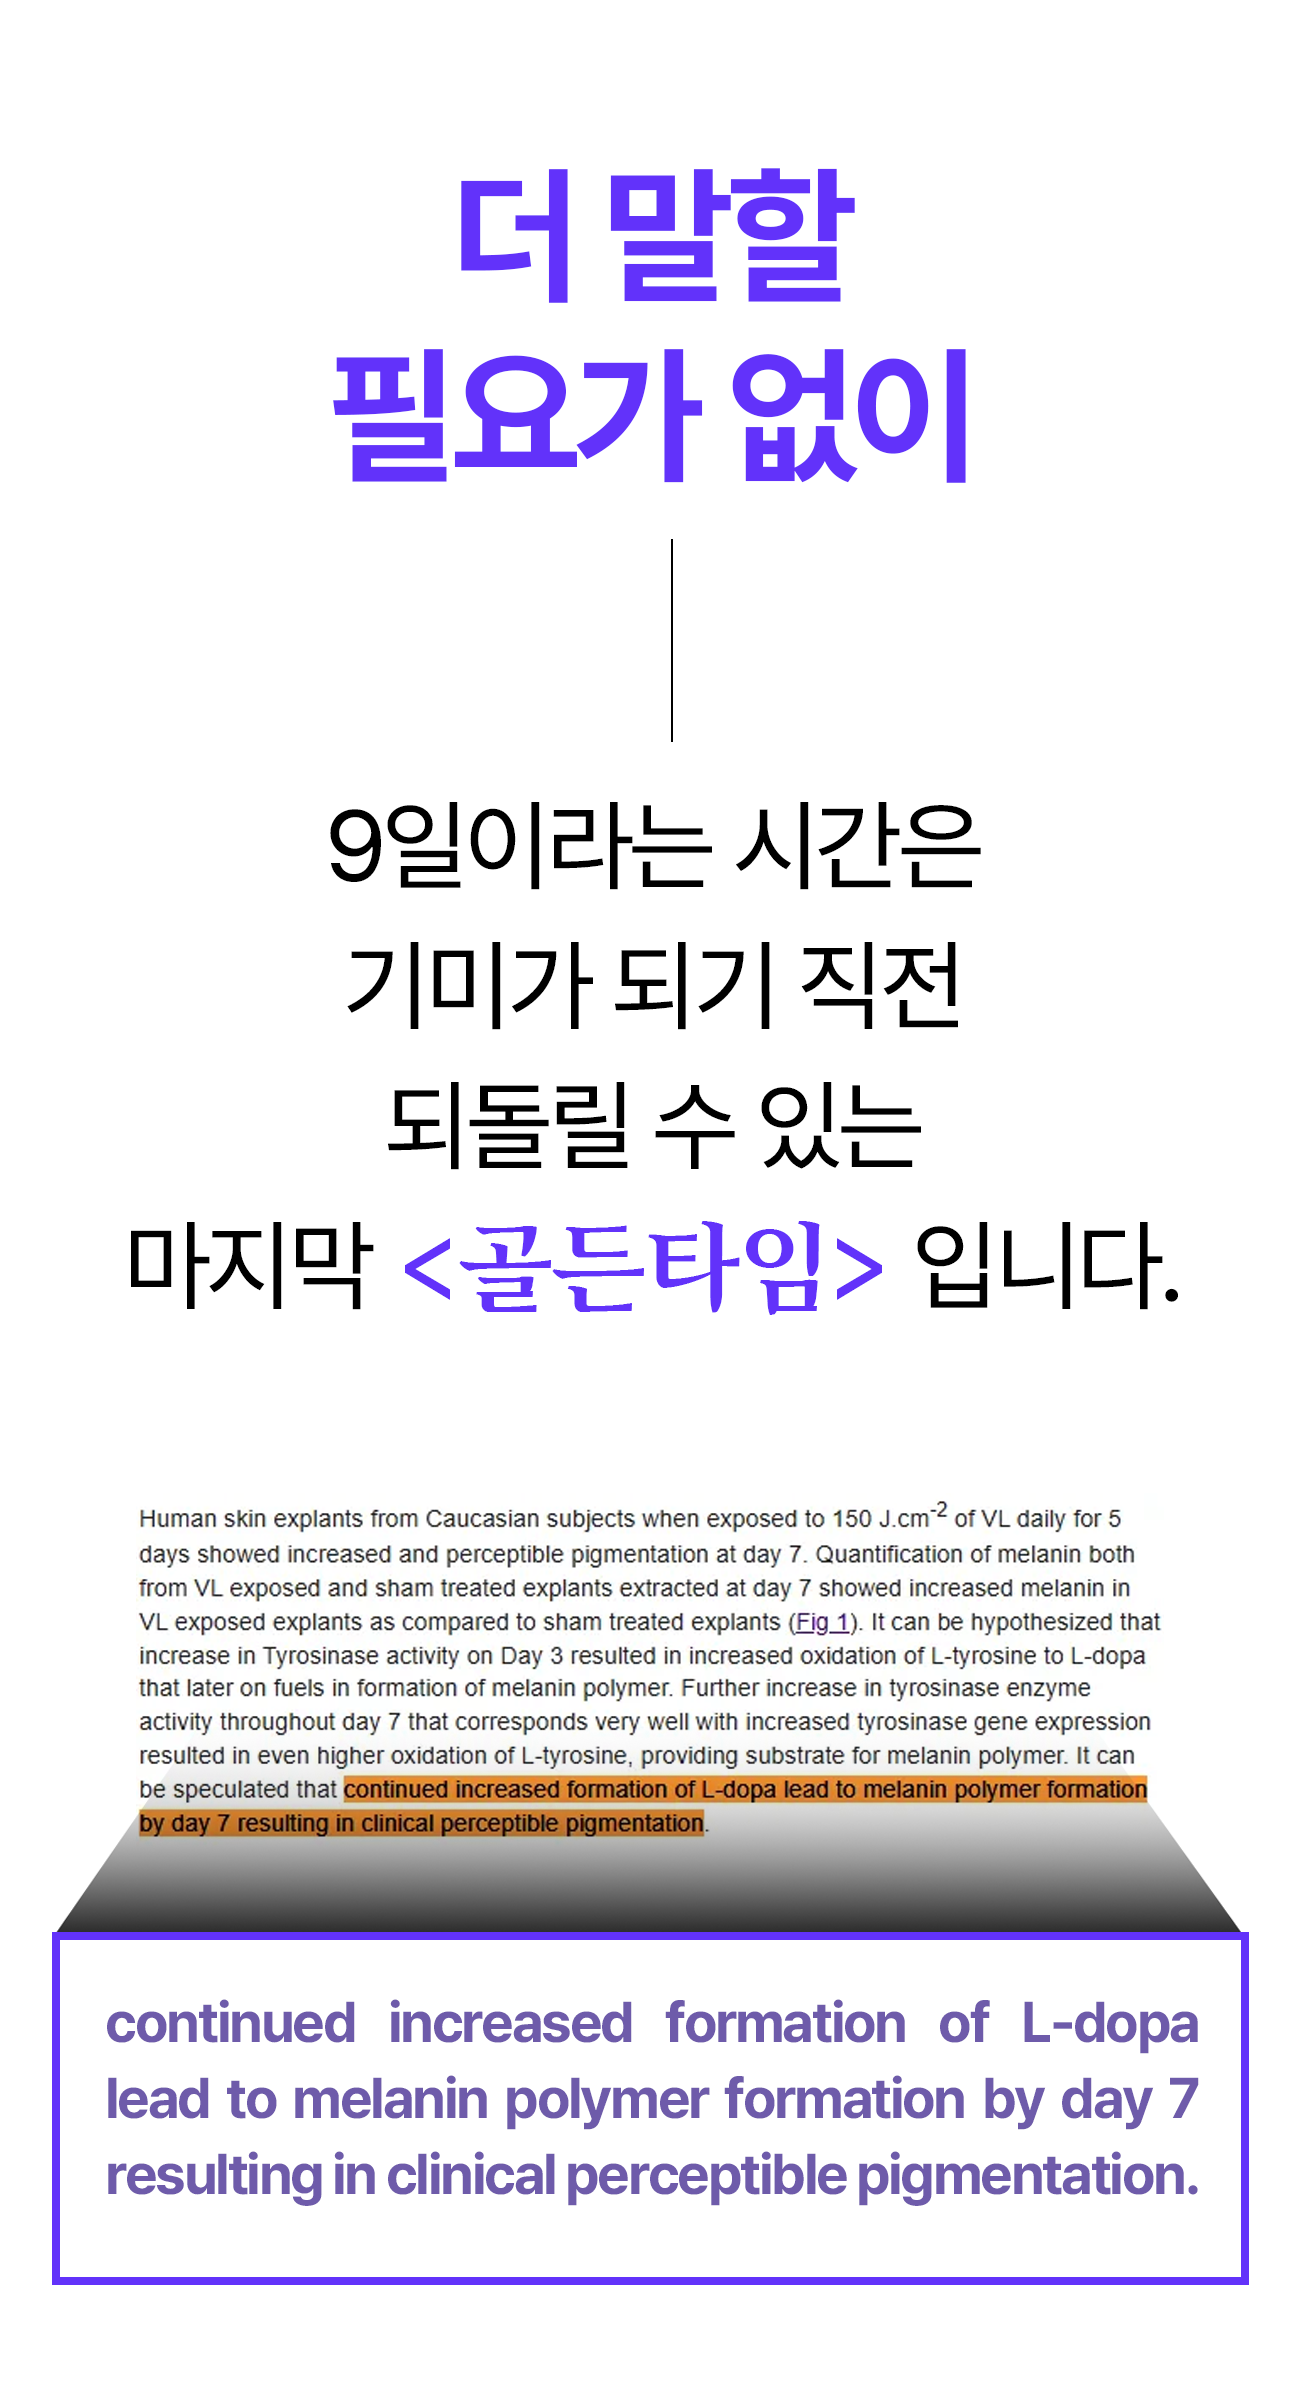

A. 실제 임상 실험과 소비자 테스트 결과, 피부톤 개선과 잡티 완화에 있어 9일 안에 변화를 체감한 사용자가 많았습니다. 물론 개인 피부 상태에 따라 차이는 있을 수 있으나, 빠른 효과를 목표로 설계된 제품입니다.